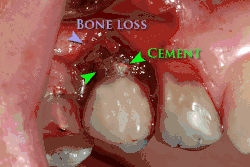

Ebenso kann eine fehlerhafte Suprakonstruktion die Periimplantitis begünstigen. Hierzu zählen eine mangelhafte Hygienefähigkeit des Implantats, Spannungen durch prothetische Fehlpassung oder Mikrobewegungen der Suprastruktur. Auch die Nichtentfernung von subgingivalen Überschüssen des Befestigungszements, mit dem die Suprakonstruktion (Zahnkrone) auf dem Implantat befestigt wird, bildet einen Entzündungsreiz, der zu einer Periimplantitis mit Knochenabbau führt.[5]

Die Diagnostik der Periimplantitis erfolgt in zwei Schritten. Zunächst erfolgt die klinische Diagnostik durch Sondierung des periimplantären Bereichs mittels Parodontalsonden. Eine auftretende Blutung, die auch von einer Eiterentleerung begleitet sein kann, führt zur Verdachtsdiagnose der Periimplantitis, die anschließend mittels Röntgenaufnahmen, bevorzugt durch intraorale Zahnfilmaufnahmen, von einer reinen Mukositis differentialdiagnostisch abgegrenzt beziehungsweise bestätigt werden kann. Die Mukositis verläuft suprakrestal, also oberhalb des Knochensaums. Die Defektklassifizierung erfolgt nach Schwarz et al.[6]